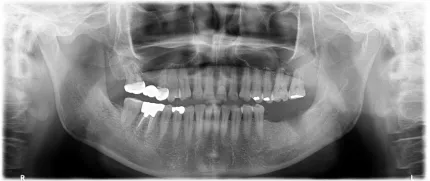

マイクロスコープやCTを利用した、より精度の高いインプラント治療

マイクロスコープというと根管治療というイメージがありますが、インプラント治療においても欠かせない医療機器です。拡大鏡下におけるインプラント周囲の歯肉移植術や上部構造装着時のセメント取り残しの確認など、精密に状態を把握できるマイクロスコープは重要です。当院ではマイクロスコープやCTを使用し、丁寧なインプラント治療を努めています。また、患者様のご希望するお口の状態をしっかりと把握し、インプラントが必要か必要でないかを納得していただいた上で治療に移りますので安心してご相談ください。

たとえば、奥歯の親知らずを前歯に再利用することはできません。条件を満たした歯でないと行うことができないのが歯の移植ですが手技として難しいものでもあり、どこの歯科医院でも行える治療ではありません。当院は歯の移植に関してもマイクロスコープやCTを駆使して症例を手掛けています。